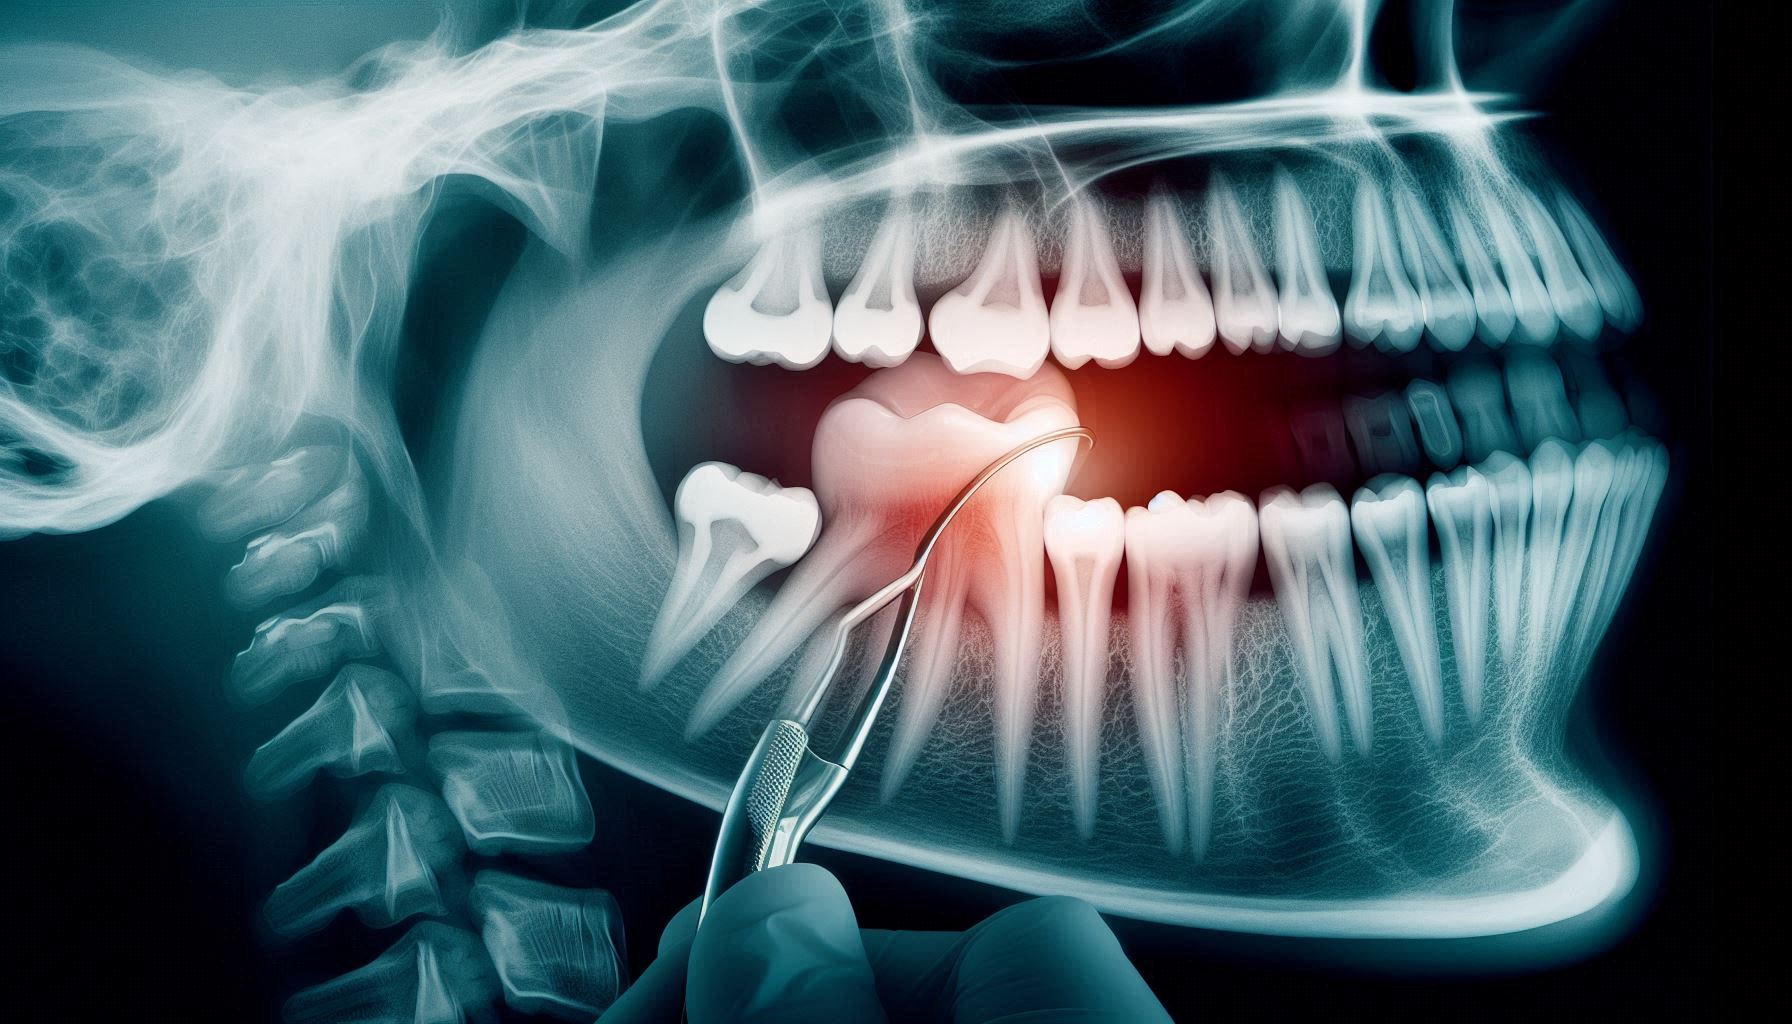

اولین قدم در تشخیص هر مشکل دهانی، معاینه بالینی است، اما دندانها ساختاری پیچیده دارند و بسیاری از عفونتها یا پوسیدگیها در عمق بافت دندان یا ریشه پنهان میشوند. در چنین شرایطی، رادیوگرافی دندان به دندانپزشک این امکان را میدهد تا تصویر کاملی از وضعیت داخلی دندان، ریشه و استخوان اطراف آن مشاهده کند.

در نتیجه، دندانپزشک میتواند تصمیم بگیرد که آیا دندان نیاز به تشخیص درمان ریشه دارد یا میتوان آن را با روشهای سادهتر مانند پرکردگی درمان کرد.

به علاوه، تصاویر رادیوگرافی در شناسایی شکستگیهای ریز، ضایعات انتهای ریشه و عفونتهای پنهان نیز نقش تعیینکنندهای دارند. این دقت بالا باعث میشود دندانپزشک از انجام درمانهای غیرضروری جلوگیری کند و تنها در موارد مورد نیاز اقدام به عصبکشی کند.

درمان ریشه یا عصبکشی، درمانی حساس و دقیق است که نیازمند آگاهی کامل از ساختار داخلی دندان است. از آنجا که کانالهای ریشه باریک و گاهی پیچیدهاند، تشخیص تعداد و مسیر دقیق آنها بدون کمک رادیوگرافی دندان غیرممکن خواهد بود.

این تصاویر به دندانپزشک نشان میدهند که عفونت تا چه اندازه پیشرفت کرده و آیا با تشخیص درمان ریشه میتوان دندان را حفظ کرد یا نیاز به درمانهای تکمیلی وجود دارد.

همچنین، در برخی موارد عفونت ممکن است تنها در نوک ریشه دیده شود. این نوع ضایعات اغلب بدون درد و علامت هستند و فقط از طریق رادیوگرافی قابل مشاهدهاند. بنابراین، حتی اگر بیمار هیچ نشانهای از درد نداشته باشد، عکس رادیوگرافی میتواند مشکلات پنهان را آشکار کند.